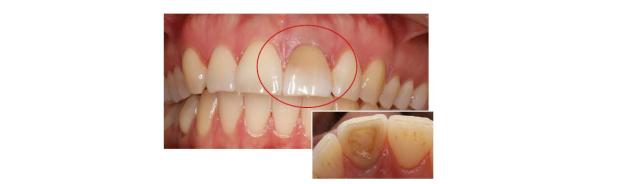

Case - Internbleking

Av: Tannlege Petter Gjessing Johnsen

Pasienten kommer grunnet ønske om å gjøre noe med tann 21. Tannen er tidligere rotfylt og har blitt misfarget ift. nabotenner, noe som plager pasienten.